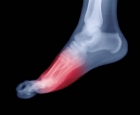

Il neuroma di Morton è una condizione dolorosa che colpisce un nervo plantare, solitamente nello spazio tra il terzo e il quarto dito del piede, caratterizzata da un ispessimento fibroso del tessuto nervoso. I sintomi tipici includono un dolore acuto, bruciante o la sensazione di camminare su un sassolino, spesso accompagnati da formicolio o intorpidimento delle dita. Sebbene i casi più severi possano richiedere interventi medico-chirurgici, alcuni

rimedi naturali possono offrire un valido supporto per alleviare la sintomatologia. Approcci come l'agopuntura possono aiutare a modulare il dolore e ridurre l'infiammazione locale, mentre la riflessologia plantare, eseguita con delicatezza evitando la pressione diretta sulla zona infiammata, può favorire il rilassamento generale del piede. Fitoterapici ad azione antinfiammatoria come l' Artiglio del diavolo (Harpagophytum) o il Ribes nero (in gemmoderapia) possono essere assunti per via orale sotto controllo di un esperto, così come l'uso locale di impacchi di argilla verde, che con la sua azione sfiammante e drenante può portare sollievo. È fondamentale, in ogni caso, associare questi rimedi a scelte pratiche, come l'utilizzo di scarpe comode con una suola ampia e un tacco basso, ed evitare i tacchi alti che comprimono l'avampiede. Si consiglia sempre di consultare un podologo o un medico per una diagnosi corretta e per affiancare questi rimedi in modo sicuro e personalizzato.